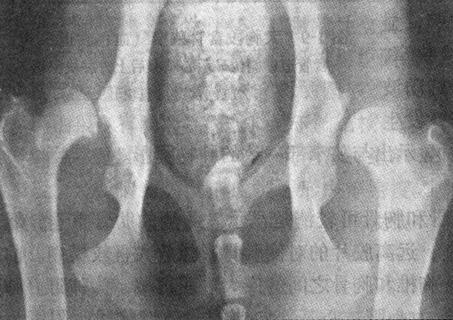

6)髋关节发育不良 该病存在于犬(多见于重型犬和大型犬)、猫、鸡、马、牛、猪、熊和大猩猩等多种动物。通常仅需一张后肢伸直位的骨盆部腹背位X现照片。如作高级评估,则尚需补充一张后肢弯曲位的骨盆部腹背位X线照片。X线表现为关节间隙增宽,髋臼与股骨头的关节面不和谐,股骨头变平、变形,髋臼变浅,股骨头半脱位或脱位(图1-6)。以股骨头圆心为起点,分别作一向对侧股骨头圆心连线和一向同侧髋臼前外侧缘连线,所形成的Norberg角小于105°(正常≥105°)。在髋臼缘,尤其在髋臼前缘,出现软骨下硬化或合并外生骨疣。股骨颈关节囊附着处有骨膜增生反应。髋关节内翻或外翻。

图1-6 犬髋关节发育不良

腹背位显示两髋臼与股骨头吻合不佳,髋臼变浅,髋臼前缘软骨下骨质硬化,股骨头蘑菇状变形,左侧髋关节半脱位,右侧髋关节脱位